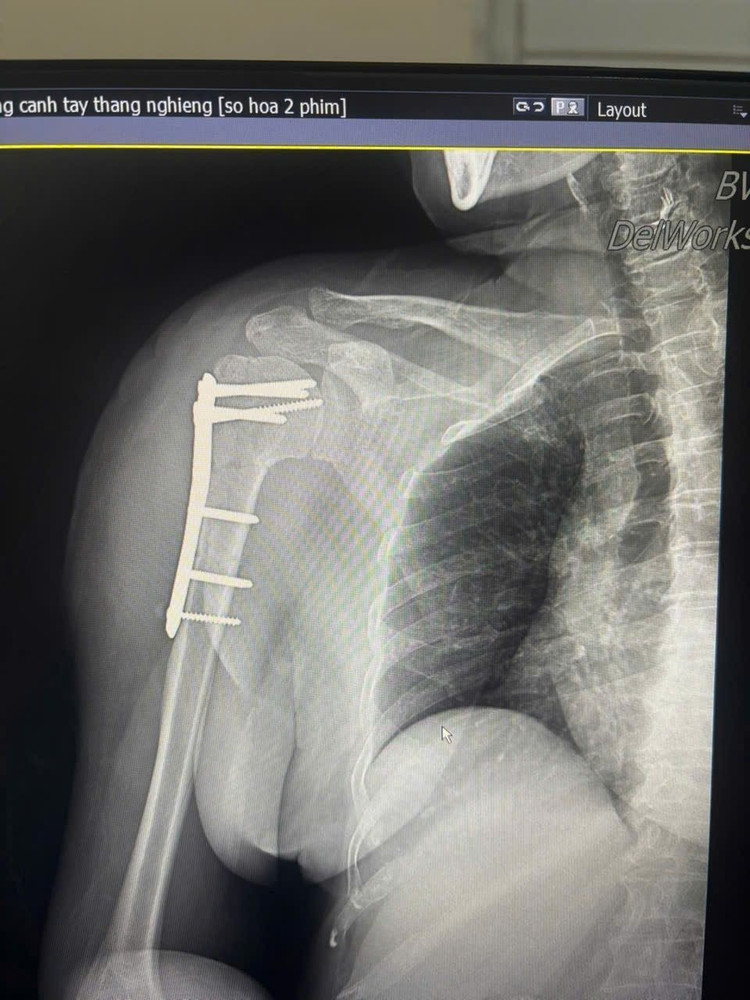

Hình ảnh gãy xương cánh tay trên phim chụp - Ảnh BVCC

Trước đó, bệnh nhân bị ngã được đưa vào viện trong tình trạng đau nhiều vùng vai phải, hạn chế vận động. Qua thăm khám lâm sàng và chẩn đoán hình ảnh, người bệnh được xác định gãy kín đầu trên xương cánh tay phải và được chỉ định phẫu thuật kết hợp xương bằng nẹp vít khóa.